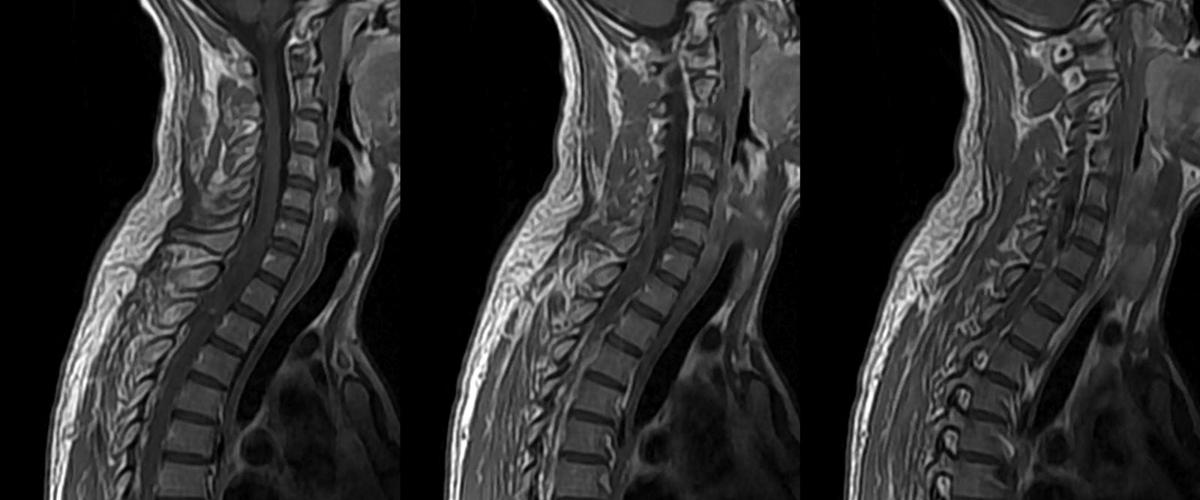

При серьезных травмах позвоночника импульсы от головного мозга не могут достичь мышц, что приводит к параличу. К сожалению, человеческий организм не способен самостоятельно регенерировать поврежденные нервные волокна. В Intel уверены, что пришло время задействовать современные технологии.

ИИ станет основой для специальных имплантов, которые вживят добровольцам с травмами спинного мозга. Устройство будет улавливать моторные и сенсорные сигналы и передавать их в обход поврежденного участка.